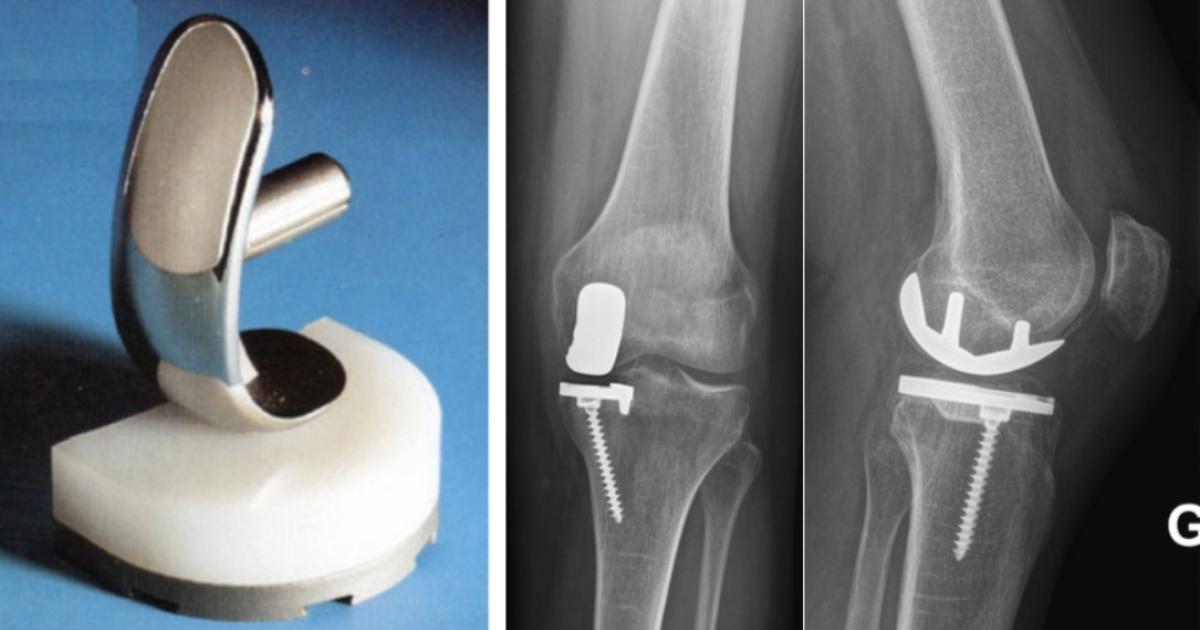

Les chirurgiens orthopédiques du CHU se forment à une meilleure pose des demi-prothèses du genou

Les pathologies orthopédiques du genou sont plus fréquentes sous nos latitudes. Le recours à des prothèses plus petites offrent une meilleure qualité de soins aux patients. Les chirurgiens du CHU perfectionnent en ce moment leur technique de pose.

Durant une semainen les équipes du service de chirurgie orthopédique sont formées sur les techniques opératoires de mise en place de la prothèse uni-compartimentale externe du genou.

Cette prothèse est utilisée pour remplacer le cartilage du genou lorsque ce dernier est usé.

Au fur et à mesure, bien que la prothèse reste inchangée les techniques pour la poser évoluent et certaines mises au point restent nécessaires.

Il s'agit d'une opération, moins lourde pour le corps, dont les bienfaits ont été mis en lumière par de nombreuses études.

En Martinique, pas moins de 115 prothèses ont été posées en 2024.